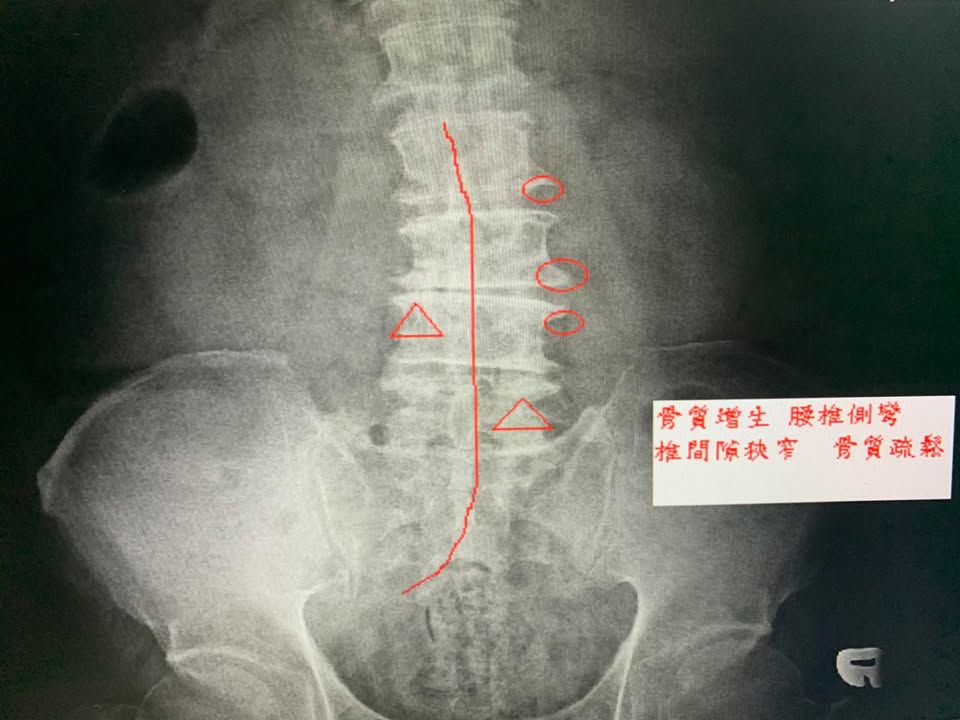

😂80多歲的林杯杯腰痛超過一年以上,腰痛連到大腿跟小腿的後側,走路無法超過5分鐘,最近這幾個月都要拿拐杖走路,無法墊腳走路,完全沒力氣墊不起來,上廁所彎腰的姿勢非常疼痛,從座位轉成站位也非常痛,經過兩個醫學中心的檢查確定追椎孔狹窄合併坐骨神經痛,因為患者的心臟病問題所以骨科醫師不太建議開刀,只能請患者拉腰跟吃止痛藥與肌肉鬆弛劑,但是腰的狀況實在是太痛了,經過友人介紹來接受腰椎整合針刀療法

✳️由於狀況實在很嚴重,徐醫師跟伯伯說先安排四次治療,如果有效再繼續做下去,如果改善不到一半可能還是要尋求骨科跟神外開刀進一步處理,非常幸運在第三次治療後就看到效果,走路疼痛感大幅度下降,以前上廁所無法彎腰擦屁股,現在都可以了,走路時間也進步很多,後來就建議伯伯把一個療程八次全部走完,很開心幫針刀醫學療法見證